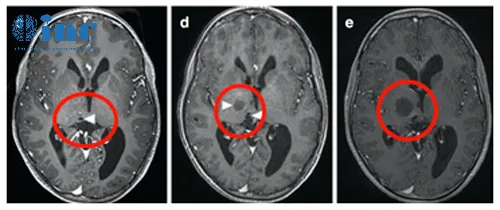

26岁足球运动员巨大丘脑占位次全切后10天出院

患者情况:在一次头部轻伤后近3个月来逐渐出现复视、肢体活动欠灵活、容易急躁,遂当地医院就诊。发现巨大丘脑占位并压迫脑干,当地医院表示,目前虽无明显肢体瘫痪症状,但是手术难度风险极大,有昏迷、失明、术后瘫痪、感觉障碍等可能,且肿瘤切除率有限。后慕名求诊于德国巴特朗菲教授。

诊断:右侧丘脑胶质母细胞瘤(胶质瘤4级),压迫右侧中脑WHO 4级,MGMT甲基化。

主刀医生:INC巴特朗菲教授

治疗后情况:在术中电生理监测(SEP和MEP)下,巴特朗菲教授采用右侧额叶旁开颅术和通过额叶纵裂经胼胝体入路,肿瘤得到次全切除。手术顺利,无围手术期并发症。术后当天拔除气管,无神经功能缺损。术后第2天转到普通病房。术后左手有轻微精细运动欠灵活,术后1周左右明显改善。术后10天出院,保持清醒,精神可,没有颅神经缺损;没有视野缺陷,肢体感觉和运动正常。

术后MR显示肿瘤次全切除,占位效应明显解除